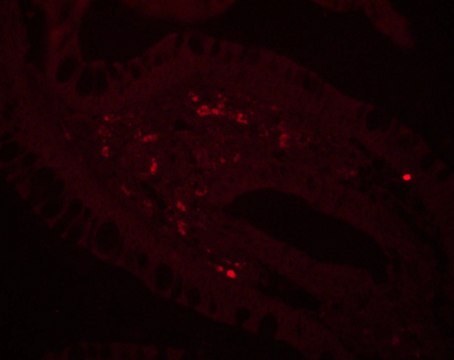

direct immunofluorescence: 1:50 using formalin-fixed, paraffin-embedded human colon carcinoma tissue